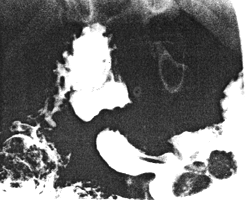

Case 36.2. A.P., girl aged 16 years, was admitted with a history of recurrent malaena (for which blood transfusions had been necessary) and symptoms of iron deficiency anaemia. On examination hyperpigmented "freckles" were seen around the mouth, on the buccal mucosa and on the fingers and feet. (Her father had similar areas of pigmentation). Other findings were a hypochromic microcytic anaemia and sedimentation rate of 20.0 mm/hr. Rectal examination revealed no abnormality but tests for stool occult blood were positive. Radiological examination showed two round, polypoid defects, each l.5cm in diameter, within the confines of the pyloric sphincteric cylinder (Fig 36.2A). The distal margins of the defects were 1.0 and 3.0cm respectively from the pyloric aperture; no stalks were seen. During contraction of the cylinder the defects moved in an orad direction, the distance from their distal margins to the pylorus increasing to 4.0cm and 5.2cm respectively (Fig 36.2B). These movements occurred regularly during the examination.

![]() |

| Fig. 36.2 B.Sphincteric cylinder contracted. The polyps have moved in an orad direction |